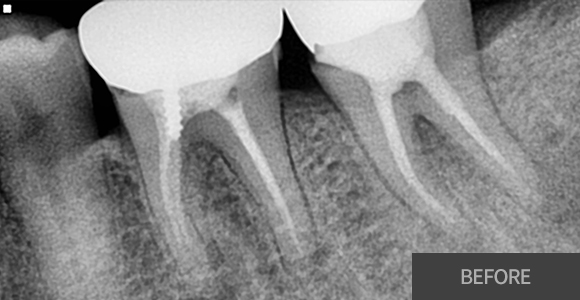

신경치료

재근관치료